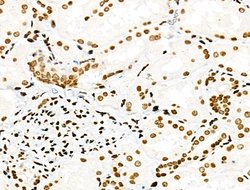

| Immunohistochemistry (Paraffin), Western Blot, Immunocytochemistry | |